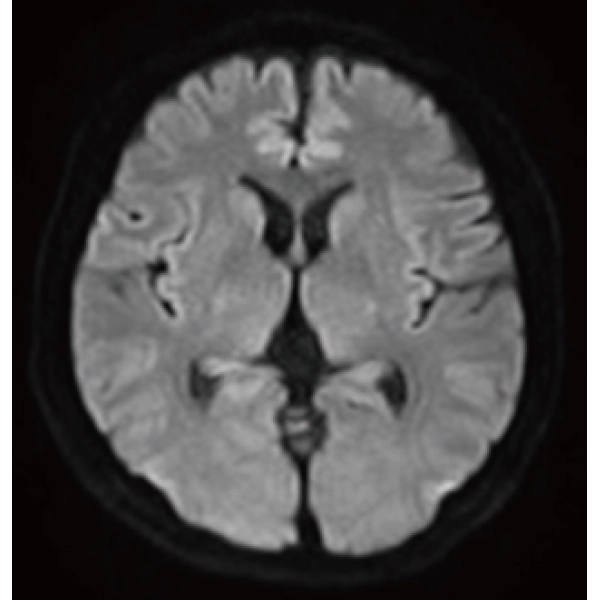

"DLR" is applicable to all body parts and promotes high speed imaging and diagnostic efficiency

IP-RAPID x DLR Plus can also shorten imaging time, allowing more images to be taken in the same examination time.

Additional imaging, such as different image types and cross sections, can be added to the conventional examination to increase the amount of information and make the diagnosis more reliable.